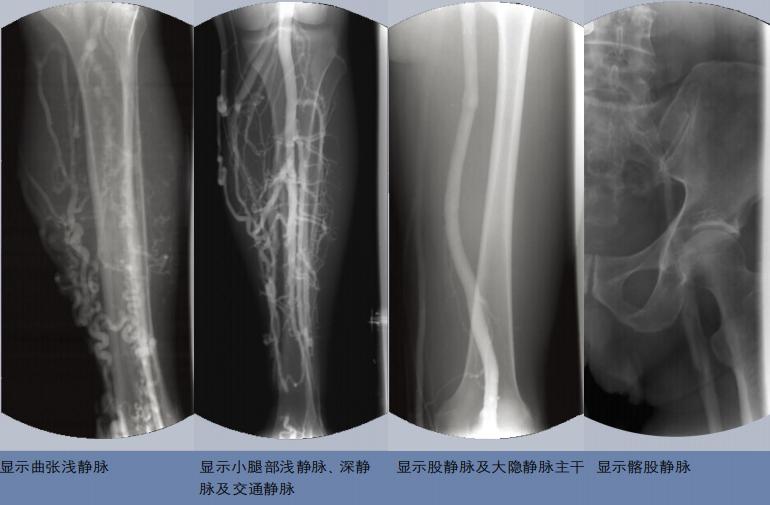

静脉造影好比描绘了一张详尽的下肢静脉系统(浅静脉、深静脉、交通静脉)“地图”,便于医师有针对性地制定手术方案,达到最佳的治疗效果。